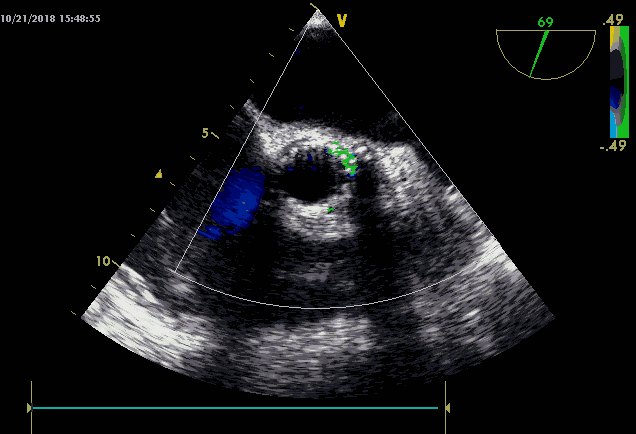

7.瓣膜释放后心超及造影显示轻中度瓣周漏;

8.选择TAV8-2126球囊后扩;

9.术后造影显示轻微瓣周漏,无返流,测跨瓣压差3-4mmHg;

10.术后心超提示瓣膜形态可,少量瓣周漏;